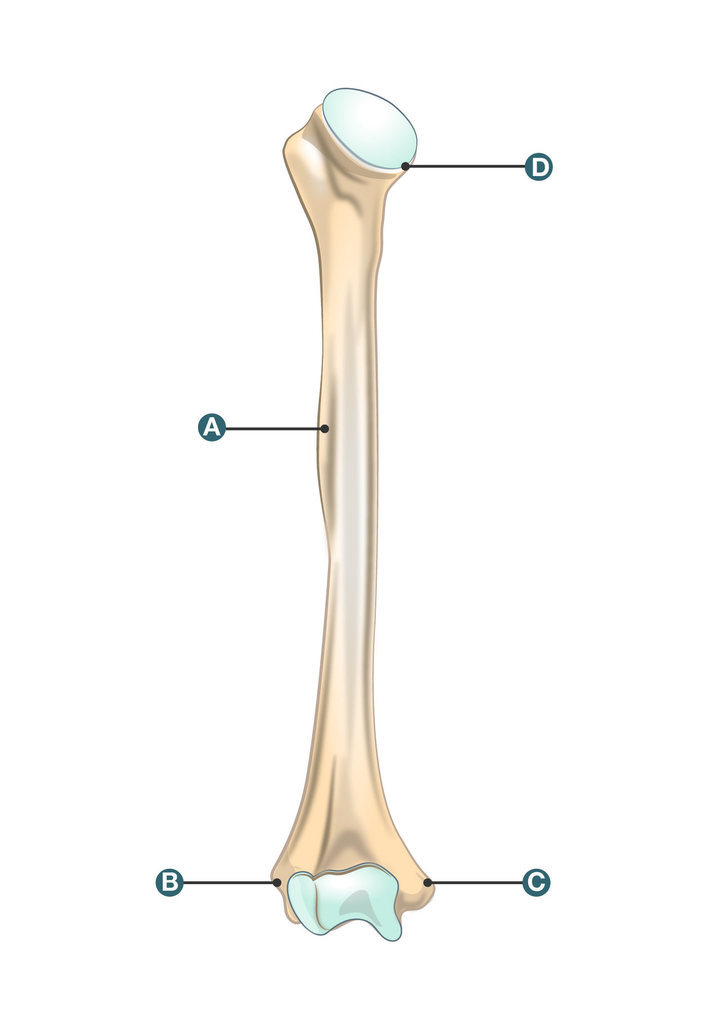

All of the following take part in the formation of the wrist joint, except: